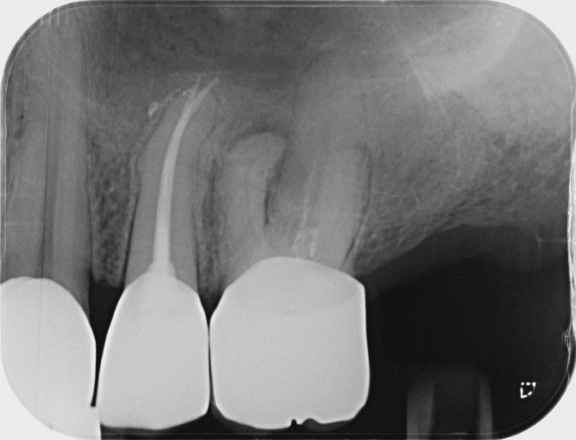

Endodontic retreatment with root perforation using MTA repair cement and MTA based sealer